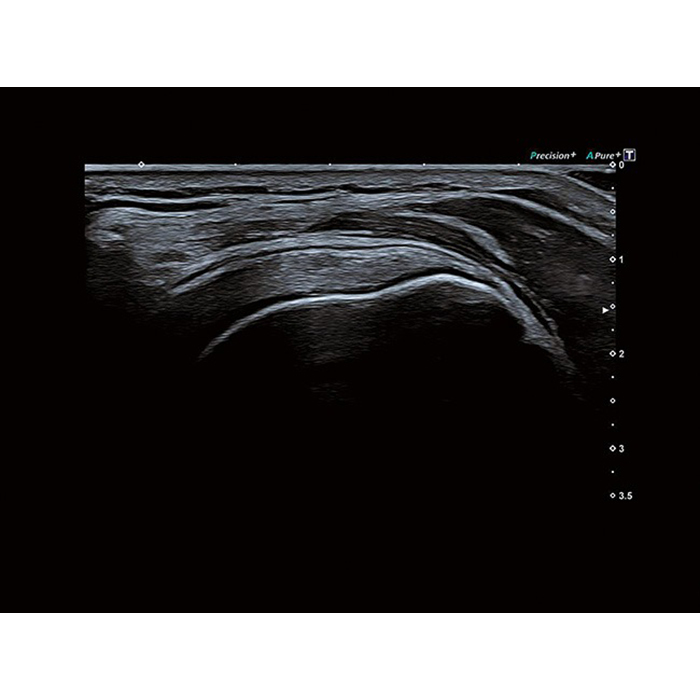

Высочайшее качество изображений и удобный интерфейс, унаследованный от самого совершенного оборудования Canon Medical, помогут обеспечить высочайшую продуктивность и скорость работы.

- Precision Imaging (прецизионная визуализация в результате получения и обработки данных от смежных сигналов))

- ApliPure+ (повышение контрастности изображений)

Технология получения и отображения информации о жесткости ткани, возможность проводить оценку динамики перфузии органов, тканей, образований, простой межреберный доступ благодаря специальным конвексным датчикам, возможность совмещать картинку в режиме реального времени с прежними данными МРТ, КТ, УЗИ, детальная визуализация плода в 1 триместре, технология трекинга миокарды и другое. Конкурентная цена и широкая продуктивность УЗ сканера Toshiba (Canon) a450 делают его покупку выгодным капиталовложением и выводят медицинское учреждение на более высокий уровень обслуживания пациентов.Область применения

- Скелетно-мышечная система